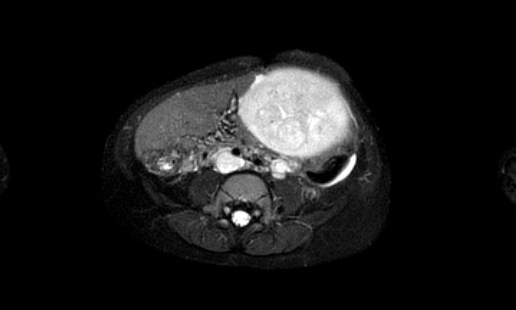

Hình ảnh MRI của một bé gái chín tháng tuổi có khối u ở bụng trái. MRI cho thấy khối u tuyến thượng thận trái, một phần đặc, một phần nang. Có nhiều di căn gan.

Khối u đã được sinh thiết. Có tình trạng chảy máu liên tục qua kim dẫn đường. Vào cuối thủ thuật, hai nút bọt gelatin đã được đặt vào (các dải tăng âm (mũi tên)).